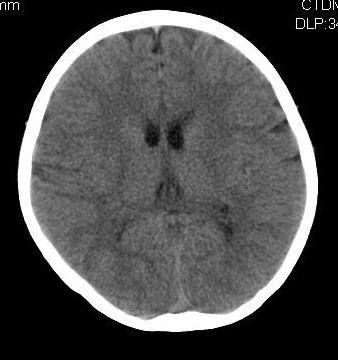

女,10岁,智力发育不良,既往史无特殊。

脑裂畸形,灰质异位